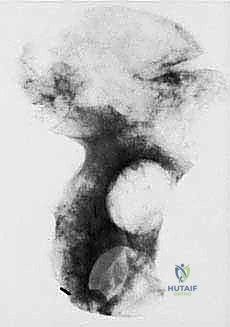

- Plain Radiography (FIG 2): While of limited value for early lesions, it provides an initial overview. As you can see in Figure 2A, we have a large lytic lesion of the right periacetabular region. Figure 2C shows a cartilage-forming lesion in the left ilium. However, plain films often underestimate the true extent of these tumors.

* CT with Intravenous Contrast and 3D Reconstruction (FIG 3): This is our workhorse for assessing bone involvement, destruction, and the critical relationship between the tumor and major pelvic blood vessels. It reveals any distortion of the pelvic anatomy and guides resectability. Figure 3A clearly shows extensive bone destruction and tumor extension into the pelvis and gluteal region. Figure 3C highlights an extensive tumor on the medial aspect of the ilium with destruction of the inner table.